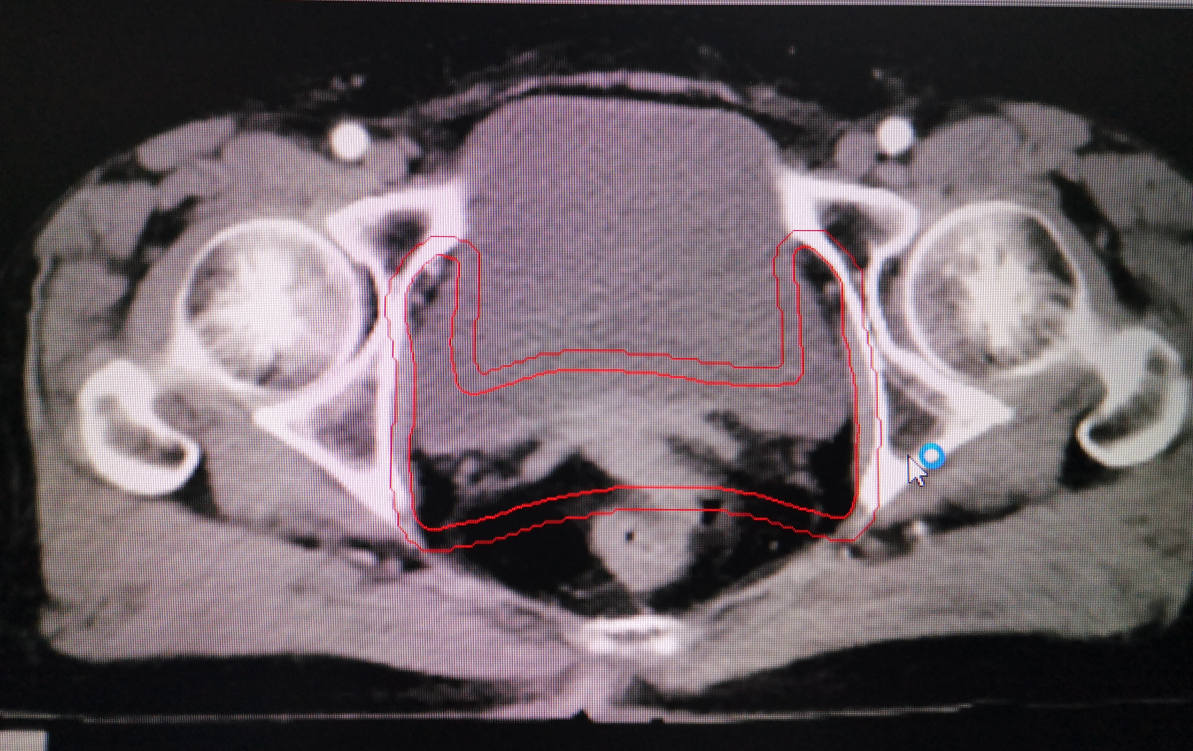

婦科腫瘤術後勾畫靶區示例: